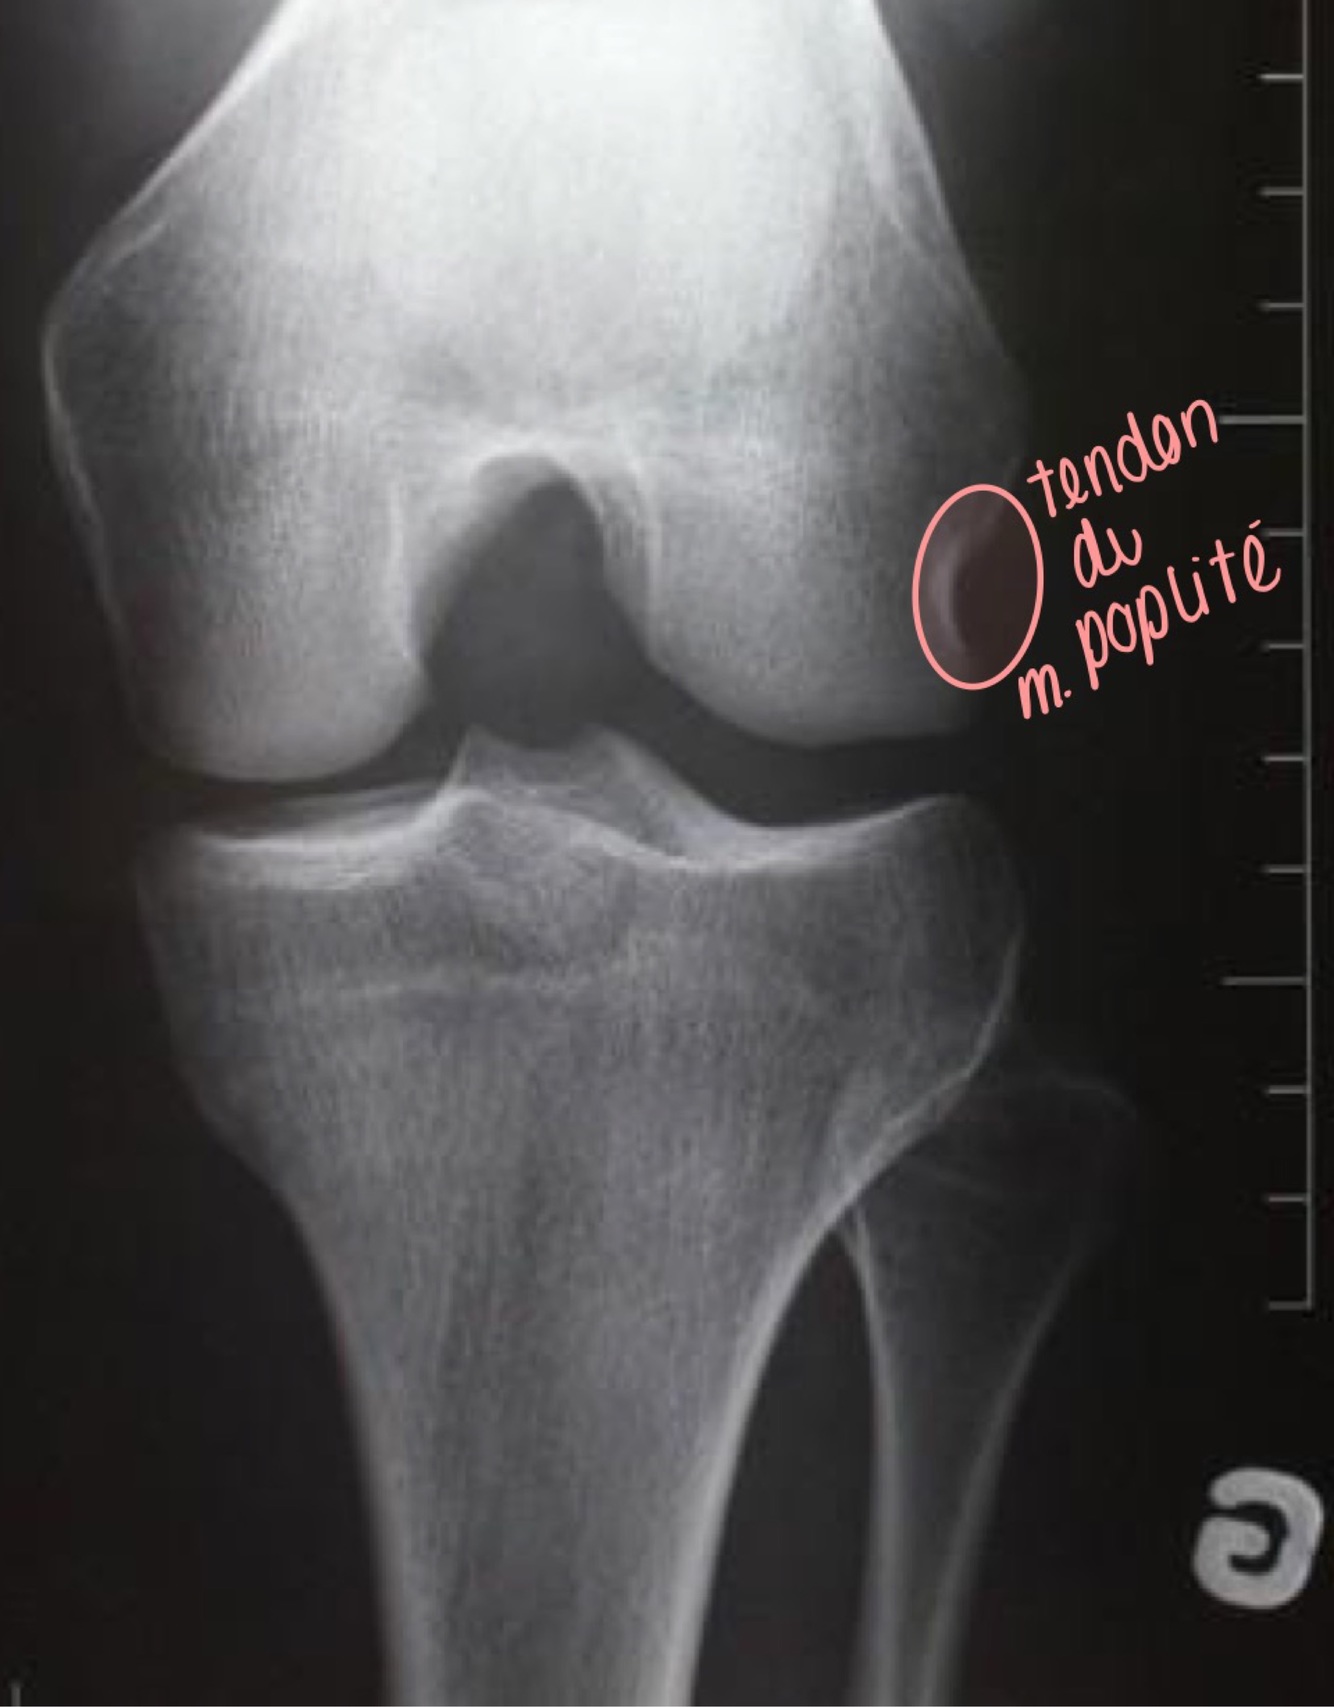

Qu’est-ce que je vois dans ma projection AP du genou

A

• La patella est surimposée au fémur

• Les espaces des compartiments interne et externe fémoro-tibiaux

sont égaux

• Léger valgus physiologique

• La tête fibulaire est surimposée au

tibia